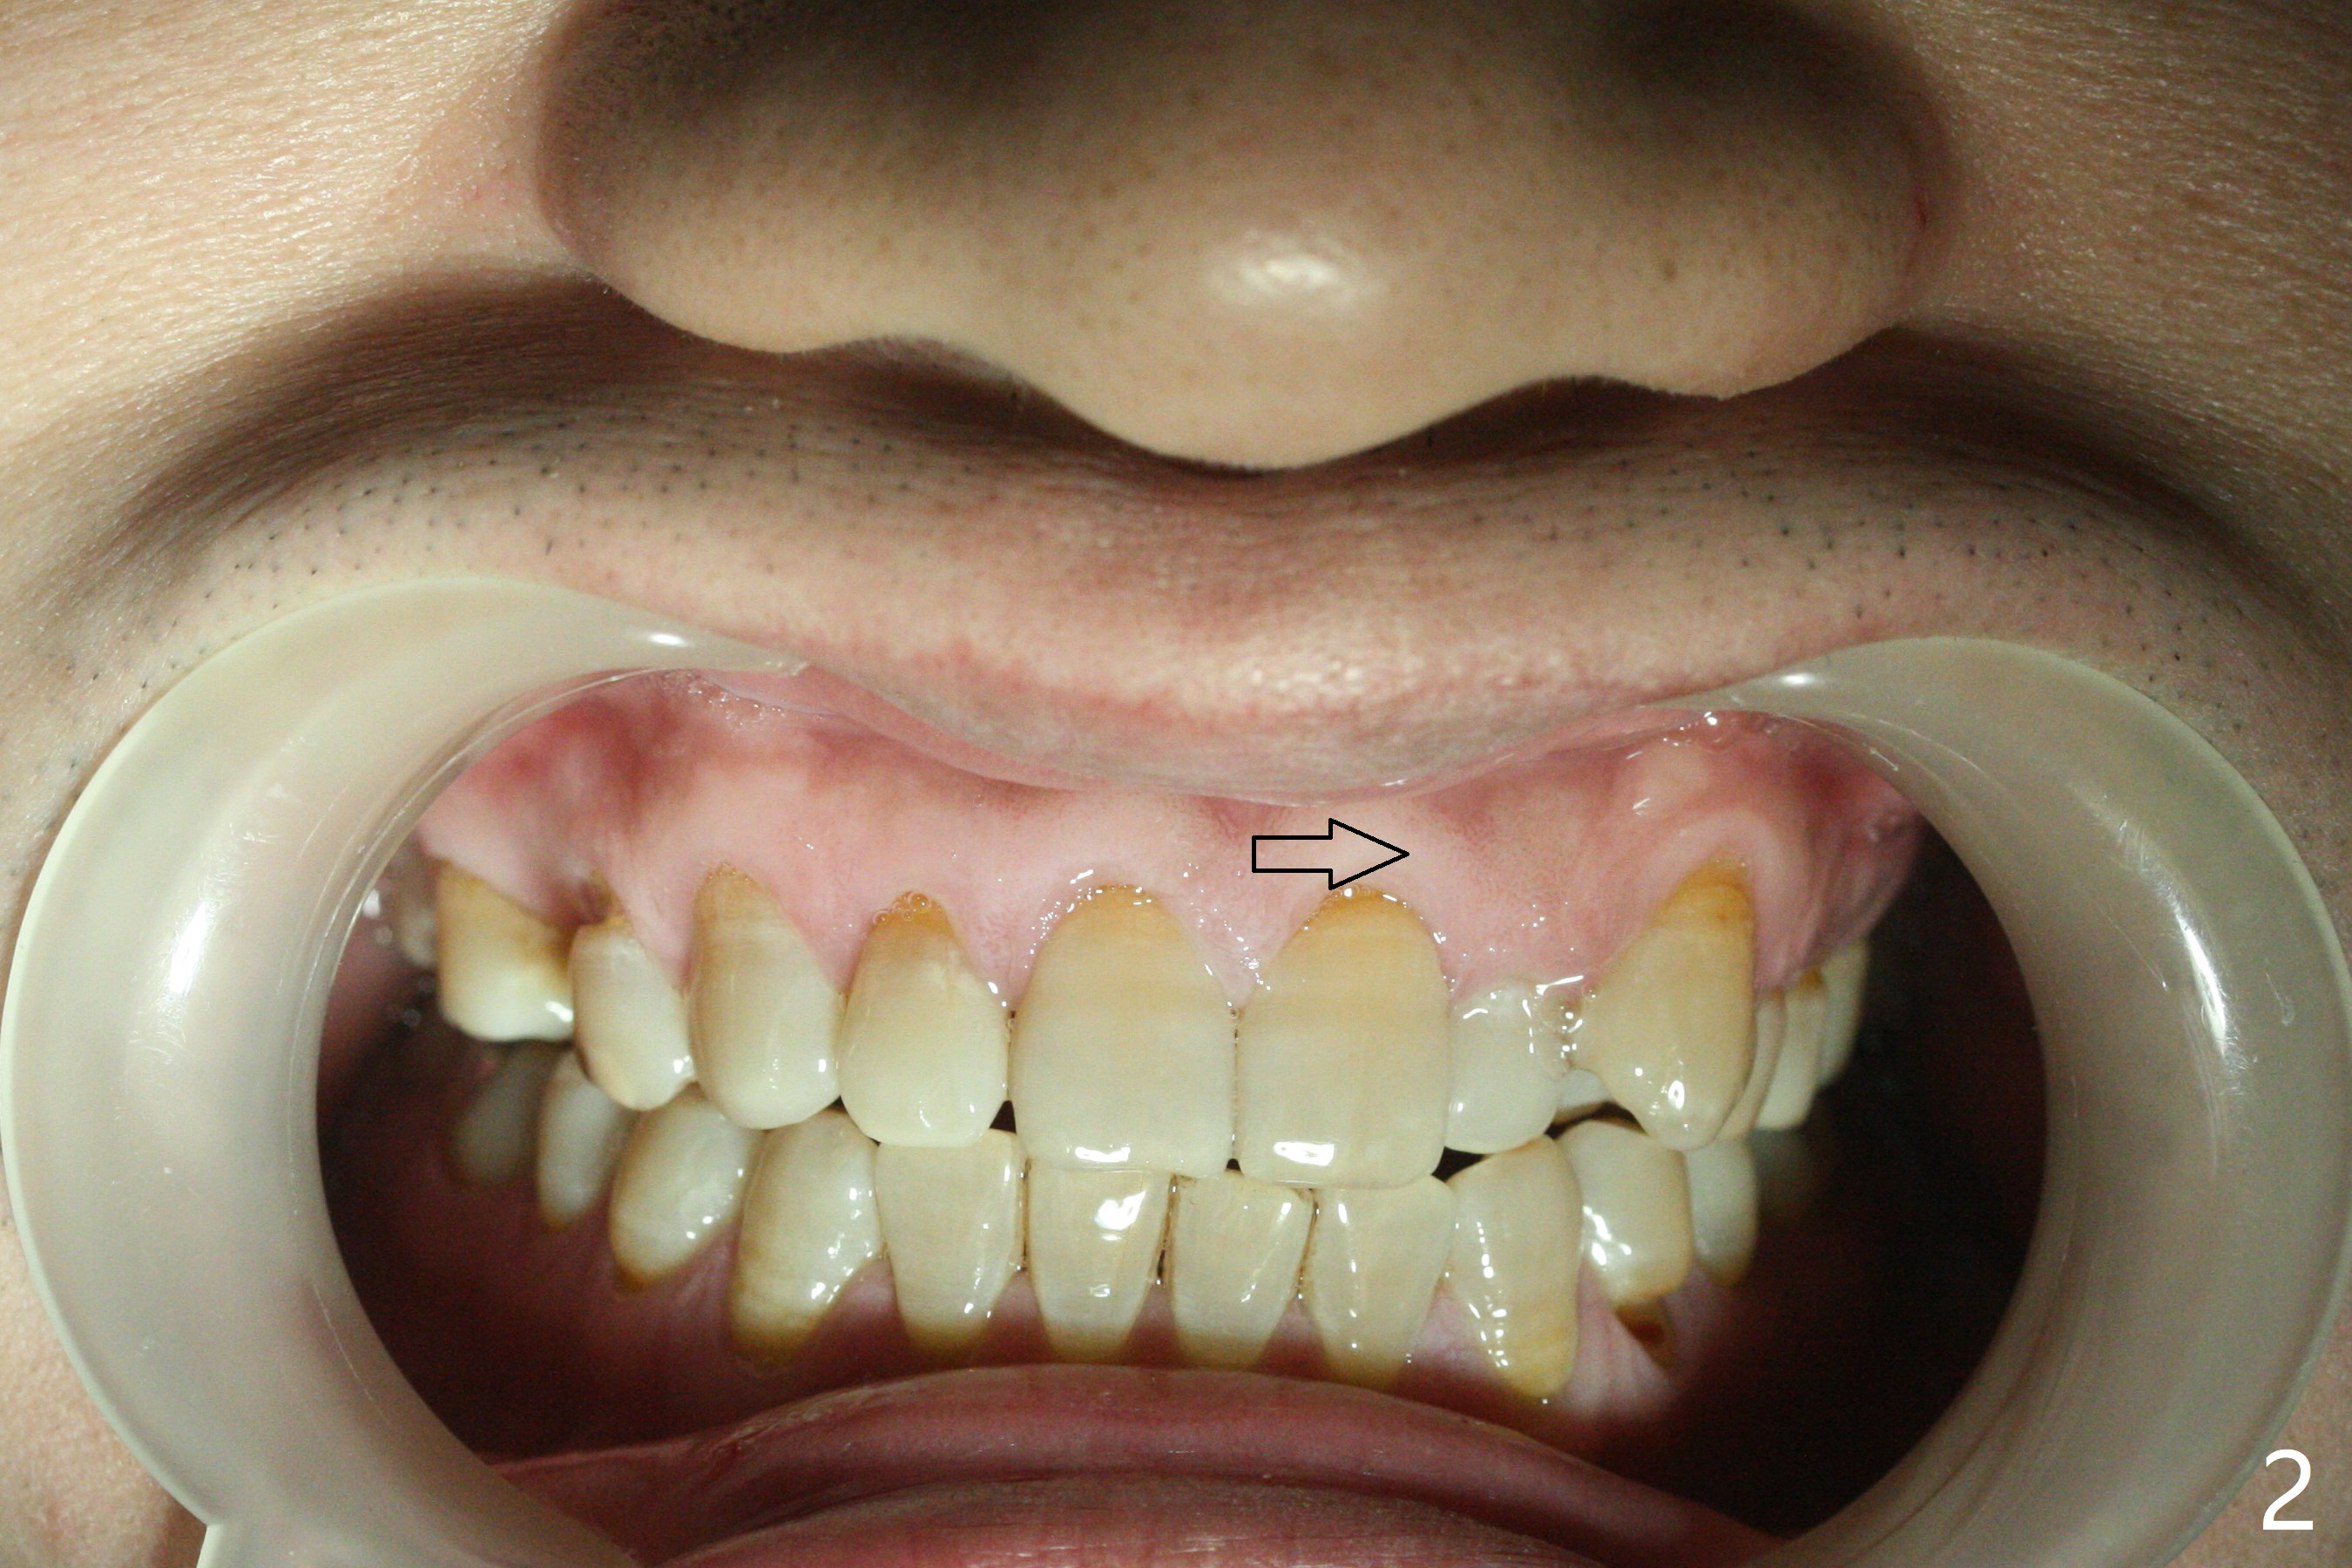

A 40-year-old man requests orthodontics after #17 and 32 extraction. UL5 is missing (Fig.1), while the upper midline deviates to the left (Fig.2 arrow) with crowding between UL2 and 3 (Fig.3). The main goal is to retract UL5 distal and move the upper midline to the right to alleviate UL anterior crowding. Implant will be not needed. To monitor potential root resorption associated with tooth movement, preop PAs are taken (Fig.4-7). The space for an implant at UR5 is narrow. UR4 needs to be distalized using UR7 or a miniimplant distal to UR7 as an anchor (Fig.8). UR4 and 3 will be repositioned to establish Class I occlusion (Fig.9). The space gained by UR4 distalization may be enough to correct the upper midline deviation and UL3 malposition (Fig.10). Brackets will be placed in the lower arch in spite of the normal alignment (Fig.11). UL2 and 3 brackets are unable to be engaged to 14 niti wire (Fig.12). Next visit try to engage UL2 bracket. If not, save the old wire for possible future reuse. Closed spring is placed with 18 ss wire <3 months post banding (coronavirus). Three weeks post closed spring between UR4-7, UR3,4 are being distalized (Fig.13). Distalization of UR4 is not much in 5.5 months (Fig.14,15). It seems necessary to use a miniimplant distal to UR7 as an anchor (Fig.16 white circle), place a long hook mesial to UL4 (more or less root movement instead of tilt) and place the same closed spring between the anchor and hook. In spite of the fact that UR4 seems to have been completely distalized and that UR2 is being distalized 8 months post banding (Fig.18), a 8 mm long mini-implant is placed in the maxillary tuberosity with minimal local anesthetic (Fig.17,19). A longer closed spring (18 mm) is placed between the implant and UR3 hook (Fig.20). Next appointment a lingual button will be placed at UR4 for rotation, while a post hook mesial to UR3 for torque. UR3 distalizes with the help of UR mini-implant, which is unfortunately loose. Next visit place lingual button at UR4 (Fig.21 arrow) to distalize the lingual cusp. Crimpable power hook is placed mesial to UR2 for distalization (for root torque, Fig.22). If it works, remove the wire and reposition the hook for UR1 next visit. UR2 is distalized in one appointment (~ 1 month, Fig.23, as compared to Fig.22). With lingual button at UR4, rotation seems to have been corrected shortly (Fig.24 arrow).